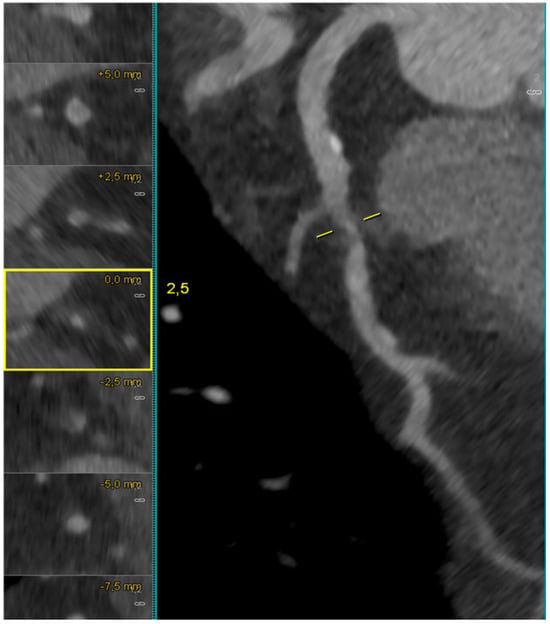

Coronary CT Angiography for PCI Planning and Guidance: A Comprehensive Narrative Review

by Lorenzo Fargione, Pietro Laforgia, Thomas Hovasse, Bernard Chevalier, Nicolas Amabile, Francesca Sanguineti, Stephane Champagne, Thierry Unterseeh, Antoinette Neylon, Neila Sayah, Jerome Garot, Lisa Simioni, Mario Togni, Stephane Cook, Hakim Benamer, Livio D’Angelo, Philippe Garot, Mariama Akodad and Ioannis Skalidis

Coronary computed tomography angiography (CCTA) is increasingly recognized as a comprehensive tool for planning percutaneous coronary intervention (PCI). By integrating plaque morphology, calcium burden, and CT-derived coronary physiology, CCTA enables non-invasive assessment of lesion complexity and supports precision-guided revascularization. This narrative review synthesizes [...] Read more.

Coronary computed tomography angiography (CCTA) is increasingly recognized as a comprehensive tool for planning percutaneous coronary intervention (PCI). By integrating plaque morphology, calcium burden, and CT-derived coronary physiology, CCTA enables non-invasive assessment of lesion complexity and supports precision-guided revascularization. This narrative review synthesizes current evidence on CT-guided PCI from original studies, registries, expert consensus documents, and international guideline recommendations. The literature was identified through PubMed, Embase, and Google Scholar, focusing on CCTA-based plaque characterization, calcium assessment, bifurcation and ostial lesions, chronic total occlusions (CTO), FFR-CT, virtual PCI simulation, and fusion imaging. Particular attention was given to contemporary investigations such as SYNTAX III, P3, and the ongoing P4 trial. CCTA reliably characterizes stenosis severity, plaque distribution, and calcification, demonstrating strong concordance with intravascular imaging. CT-based measurements support accurate stent sizing, prediction of calcium modification requirements, and identification of high-risk features in bifurcation and ostial disease. In CTO PCI, CCTA enhances visualization of proximal cap morphology, occlusion length, tortuosity, and distal vessel quality, outperforming angiographic scoring systems. CT-derived physiology and virtual PCI planning improve lesion selection and allow prediction of post-PCI hemodynamics. Emerging technologies—including photon-counting CT, artificial intelligence-assisted plaque analysis, and CT–fluoroscopy fusion—further expand the applicability of CT-guided PCI. The ongoing P4 trial is expected to provide definitive validation of CT-guided PCI and may support its incorporation into routine clinical workflows. Full article